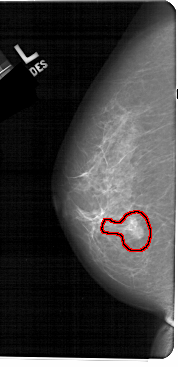

FILE: A_1243_1.LEFT_MLO.OVERLAY

TOTAL_ABNORMALITIES 1

ABNORMALITY 1

LESION_TYPE CALCIFICATION TYPE FINE_LINEAR_BRANCHING DISTRIBUTION LINEAR

LESION_TYPE MASS SHAPE OVAL MARGINS ILL_DEFINED

ASSESSMENT 5

SUBTLETY 4

PATHOLOGY MALIGNANT

TOTAL_OUTLINES 1

BOUNDARY